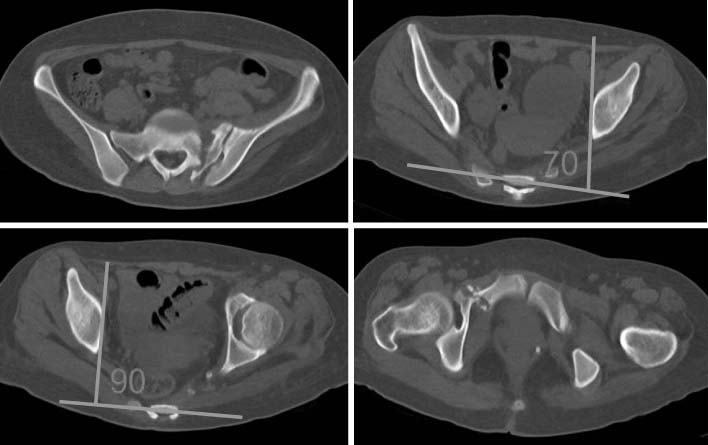

Fig. 2

Radiographs show posterior translation of the left hemipelvis on anteroposterior and inlet view and 5.5 cm significant superior migration of the left hemipelvis on outlet view. LLD: limb length discrepancy.

Fig. 2 Radiographs show posterior translation of the left hemipelvis on anteroposterior and inlet view and 5.5 cm significant superior migration of the left hemipelvis on outlet view. LLD: limb length discrepancy.